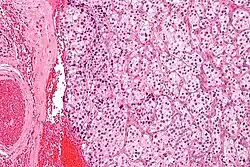

| Micrograph of a carotid body tumor (a type of paraganglioma) | |

On microscopic inspection, the tumor cells are readily recognized. Individual tumor cells are polygonal to oval and are arranged in distinctive cell balls, called Zellballen.[9] These cell balls are separated by fibrovascular stroma and surrounded by sustentacular cells.

By light microscopy, the differential diagnosis includes related neuroendocrine tumors, such as carcinoid tumor, neuroendocrine carcinoma, and medullary carcinoma of the thyroid.

With immunohistochemistry, the chief cells located in the cell balls are positive for chromogranin, synaptophysin, neuron specific enolase, serotonin, neurofilament and Neural cell adhesion molecule; they are S-100 protein negative. The sustentacular cells are S-100 positive and focally positive for glial fibrillary acidic protein. By histochemistry, the paraganglioma cells are argyrophilic, periodic acid Schiff negative, mucicarmine negative, and argentaffin negative.

Micrograph of a carotid body tumor -